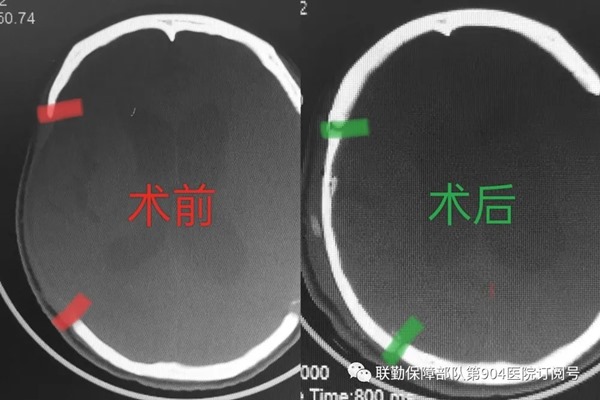

病 例 回 顾 半年前,郝女士因车祸致头部外伤命悬一线,在外院急诊行“开颅血肿清除木+双侧去骨减压术”,术后双侧颅骨缺失。一个月后,郝女士家属经病友介绍转至第904医院常州医疗区继续治疗,通过早期康复和高压氧治疗,患者情况有了好转,经过几个月的诊治护理,双方建立了良好的医患关系。近日,郝女士家属再次来院找到神经外科裴荣权主任,为求自体颅骨回植和进一步康复入院治疗。 01 快速处置 因自体颅骨回植手术之前科室并未开展过,在接到家属请求后,裴荣权主任对此次特殊的颅骨修补术高度重视,立即联系颅脑学科群施栋良主任进行了手术讨论,手术指征明确,预行手术治疗。裴主任及时向医疗区党委汇报,在医疗区党委的积极支持下快速完成了术前相关审批手续,经过明确的术前评估、过程讨论,以及充分的术前准备,手术开展顺利,这是第904医院常州医疗区首例超低温保存的自体颅骨修补术。 02 手术介绍 该手术是自体颅骨利用超低温技术保存,经后期打磨、包、消毒后再用于手术操作的一个过程。本次手术时长2小时,手术医生通过快速的分离原皮瓣,有效的清理显露原骨窗,并经过彻底止血处理后将原骨瓣放入骨窗。因为是原自体骨瓣,骨瓣与骨窗完全吻合,再行钻孔悬吊硬脑膜于骨瓣上,周边用颅骨连接片及螺钉固定,放置负压引流并缝合头皮;手术用时短,塑形效果佳。目前患者术后恢复良好,头部外观恢复完美,家属对手术效果十分满意。